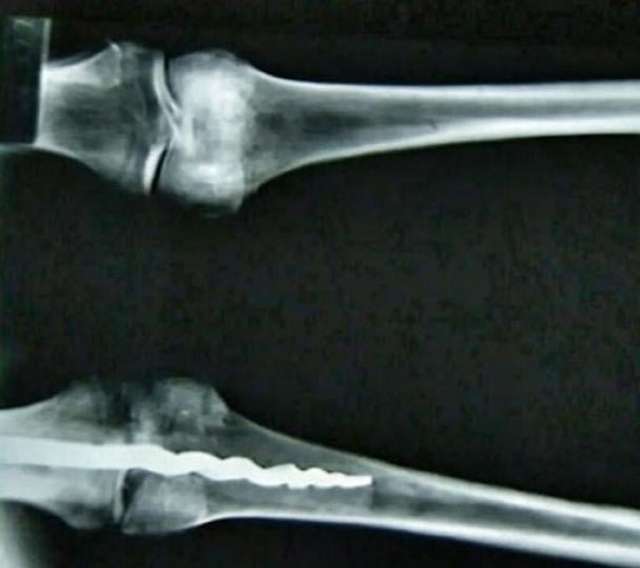

Всередині лівого коліна знаходився 9-дюймовий металевий ортопедичний штифт, який вставлений у кістку за такими біомеханічними принципами, що спочатку науковці не могли відрізнити його від сучасної процедури. Дослідження продовжилися.

У серпні 1995 року професор Вілфред Ґріґґз з Університету Бріґама Янґа показав рентгенівські знімки шести мумій, які зберігалися у каліфорнійському Музеї Розенкрейцерів Сан-Хосе. Цим було доведено хірургічне втручання у давні часи.

У звіті команди вчених стверджується, що штифт звужується, коли входить у стегнову кістку, подібно до біомеханічних методів, що стали використовувати лише у XX столітті. Інший його кінець, який розташований у великогомілковій кістці, має три фланці, – виходять назовні від серцевини штифта для запобігання обертання штифта всередині кістки.